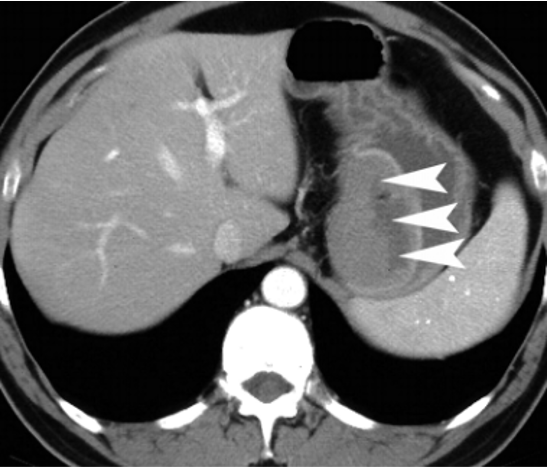

A. A well-defined, heterogeneously enhancing lesion seen in the D3 segment of the duodenum.

B. Few internal non-enhancing areas are seen in the superior aspect of the lesion.

C. A focal defect seen in the inferior aspect of the lesion, suggestive of ulceration.